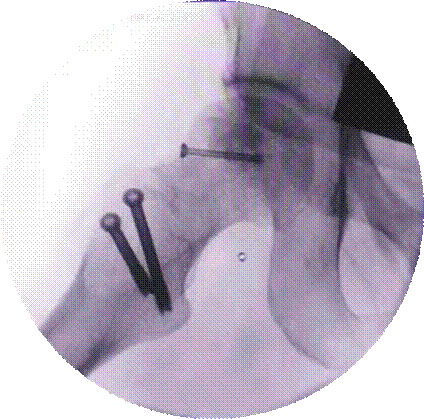

寰枢椎固定融合术治疗颅底凹陷、齿状突骨折等

特点:手术风险高。

2、脊柱手术微创化理念:采用椎间孔镜等脊柱微创手段实施各种脊柱微创手术。治愈了大量的腰间盘突出症、腰椎管狭窄症、颈椎病患者。采用PVP、PKP术治愈了大量高龄脊柱压缩性骨折患者,近年来累计完成4000例该微创手术。60%的脊柱病人可以进行微创手术,具有创伤小、效果好、安全性高、恢复快、术后不需长期卧床等特点。微创手术保持极高的优良率与可靠性。脊柱微创技术居于淮海经济区先进水平。我院在淮海经济区率先开展颈椎微创手术。

能广泛开展颈胸腰骶椎各入路手术。脊椎人工椎体置换、上颈椎入路手术、颈椎及腰椎微创手术、脊柱畸形矫形手术、脊柱结核病灶刮出术、脊椎肿瘤切除术等。